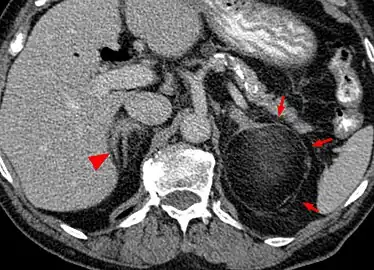

Myeloplipoma shown on a CT scan image

a)CT scan showing heterogeneous bilateral myelolipomas b) macroscopic aspect of left adrenal myelolipomas

Most myelolipomas are unexpected findings on CT scans and MRI scans of the abdomen. They may sometimes be seen on a plain X-ray films.[4]